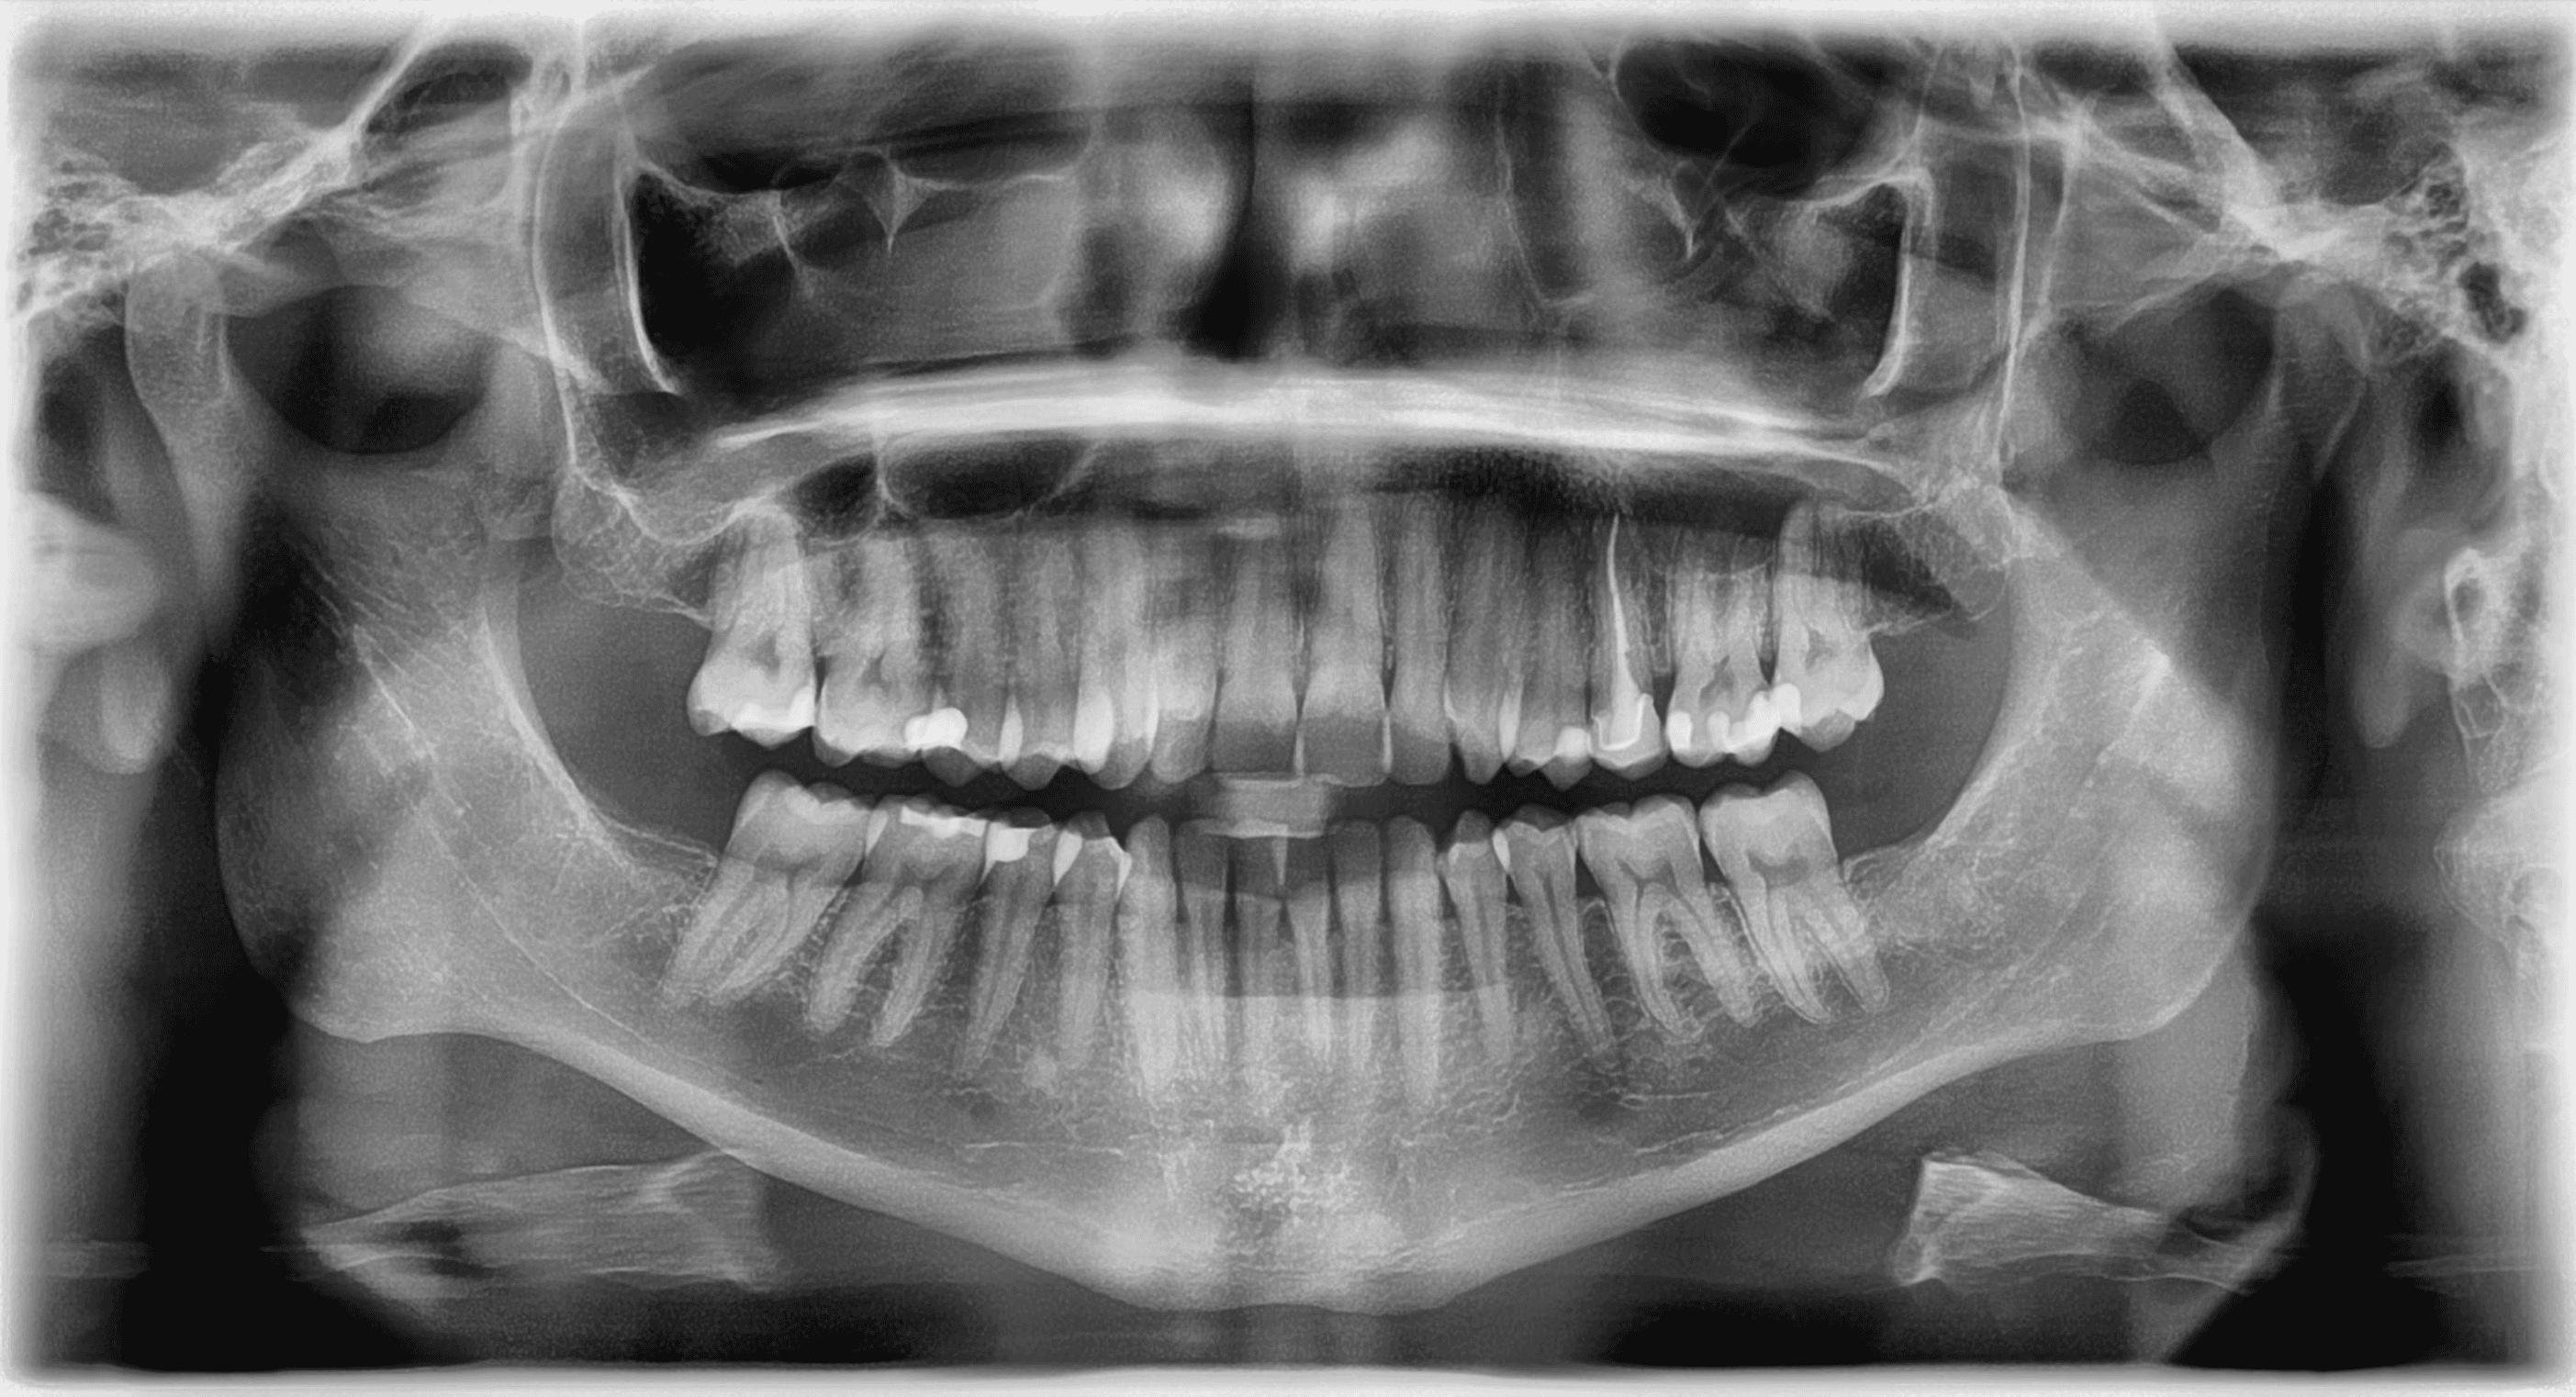

Initial treatment

X-RAYS